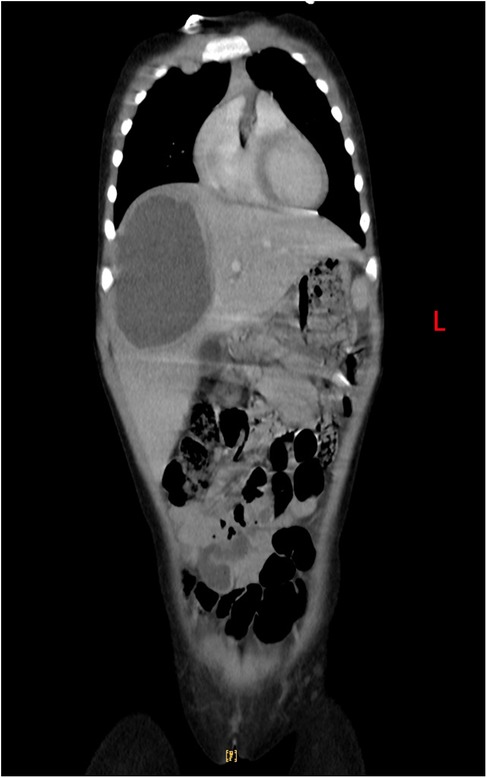

At the same time, there was still high suspicion of a tumor or autoimmune disease. Serum tests for 17 autoantibodies were performed, all yielding negative results. Enhanced thoraco-abdominal CT imaging revealed inflammation in the upper lobe of the right lung and the lower lobes of both lungs, with consolidation in the posterior segment of the right upper lobe and partial thickening of the bilateral pleura. Abdominal imaging indicated hepatomegaly (measuring 8.4 cm × 6.3 cm × 8.5 cm) and a suspected abscess in the anterosuperior segment of the right lobe of the liver (Figure 2). Given the persistence of high fever, abdominal pain, worsening dyspnea, and pronounced hepatomegaly, the patient was referred for surgery prior to definitive characterization of the liver abscess. She underwent right partial hepatectomy, drainage of the liver abscess, and intestinal adhesiolysis. Bacterial cultures of the peritoneal drainage fluid were negative. However, chest radiography 4 days postsurgery revealed a right pleural effusion, which was managed with thoracic puncture and drainage for 3 days. Pleural fluid analysis showed nucleated cells at 1,200 × 106/L, with 55% polymorphonuclear cells, 35% mononuclear cells, 1,490 × 10⁶/L red blood cells, total protein of 51 g/dL, albumin of 32.7 g/dL, lactate dehydrogenase of 795 IU/L, and adenosine deaminase of 11.9 IU/L, with the presence of pyocytes. Pleural fluid culture was negative. Immunohistochemical analysis of liver necrotic tissue confirmed the presence of amebic trophozoites, thereby establishing the diagnosis of ALA. The patient's fever resolved 12 days postoperation.

Figure 2. Enhanced thoraco-abdominal CT shows a suspected abscess in the anterosuperior segment of the right lobe of the liver.